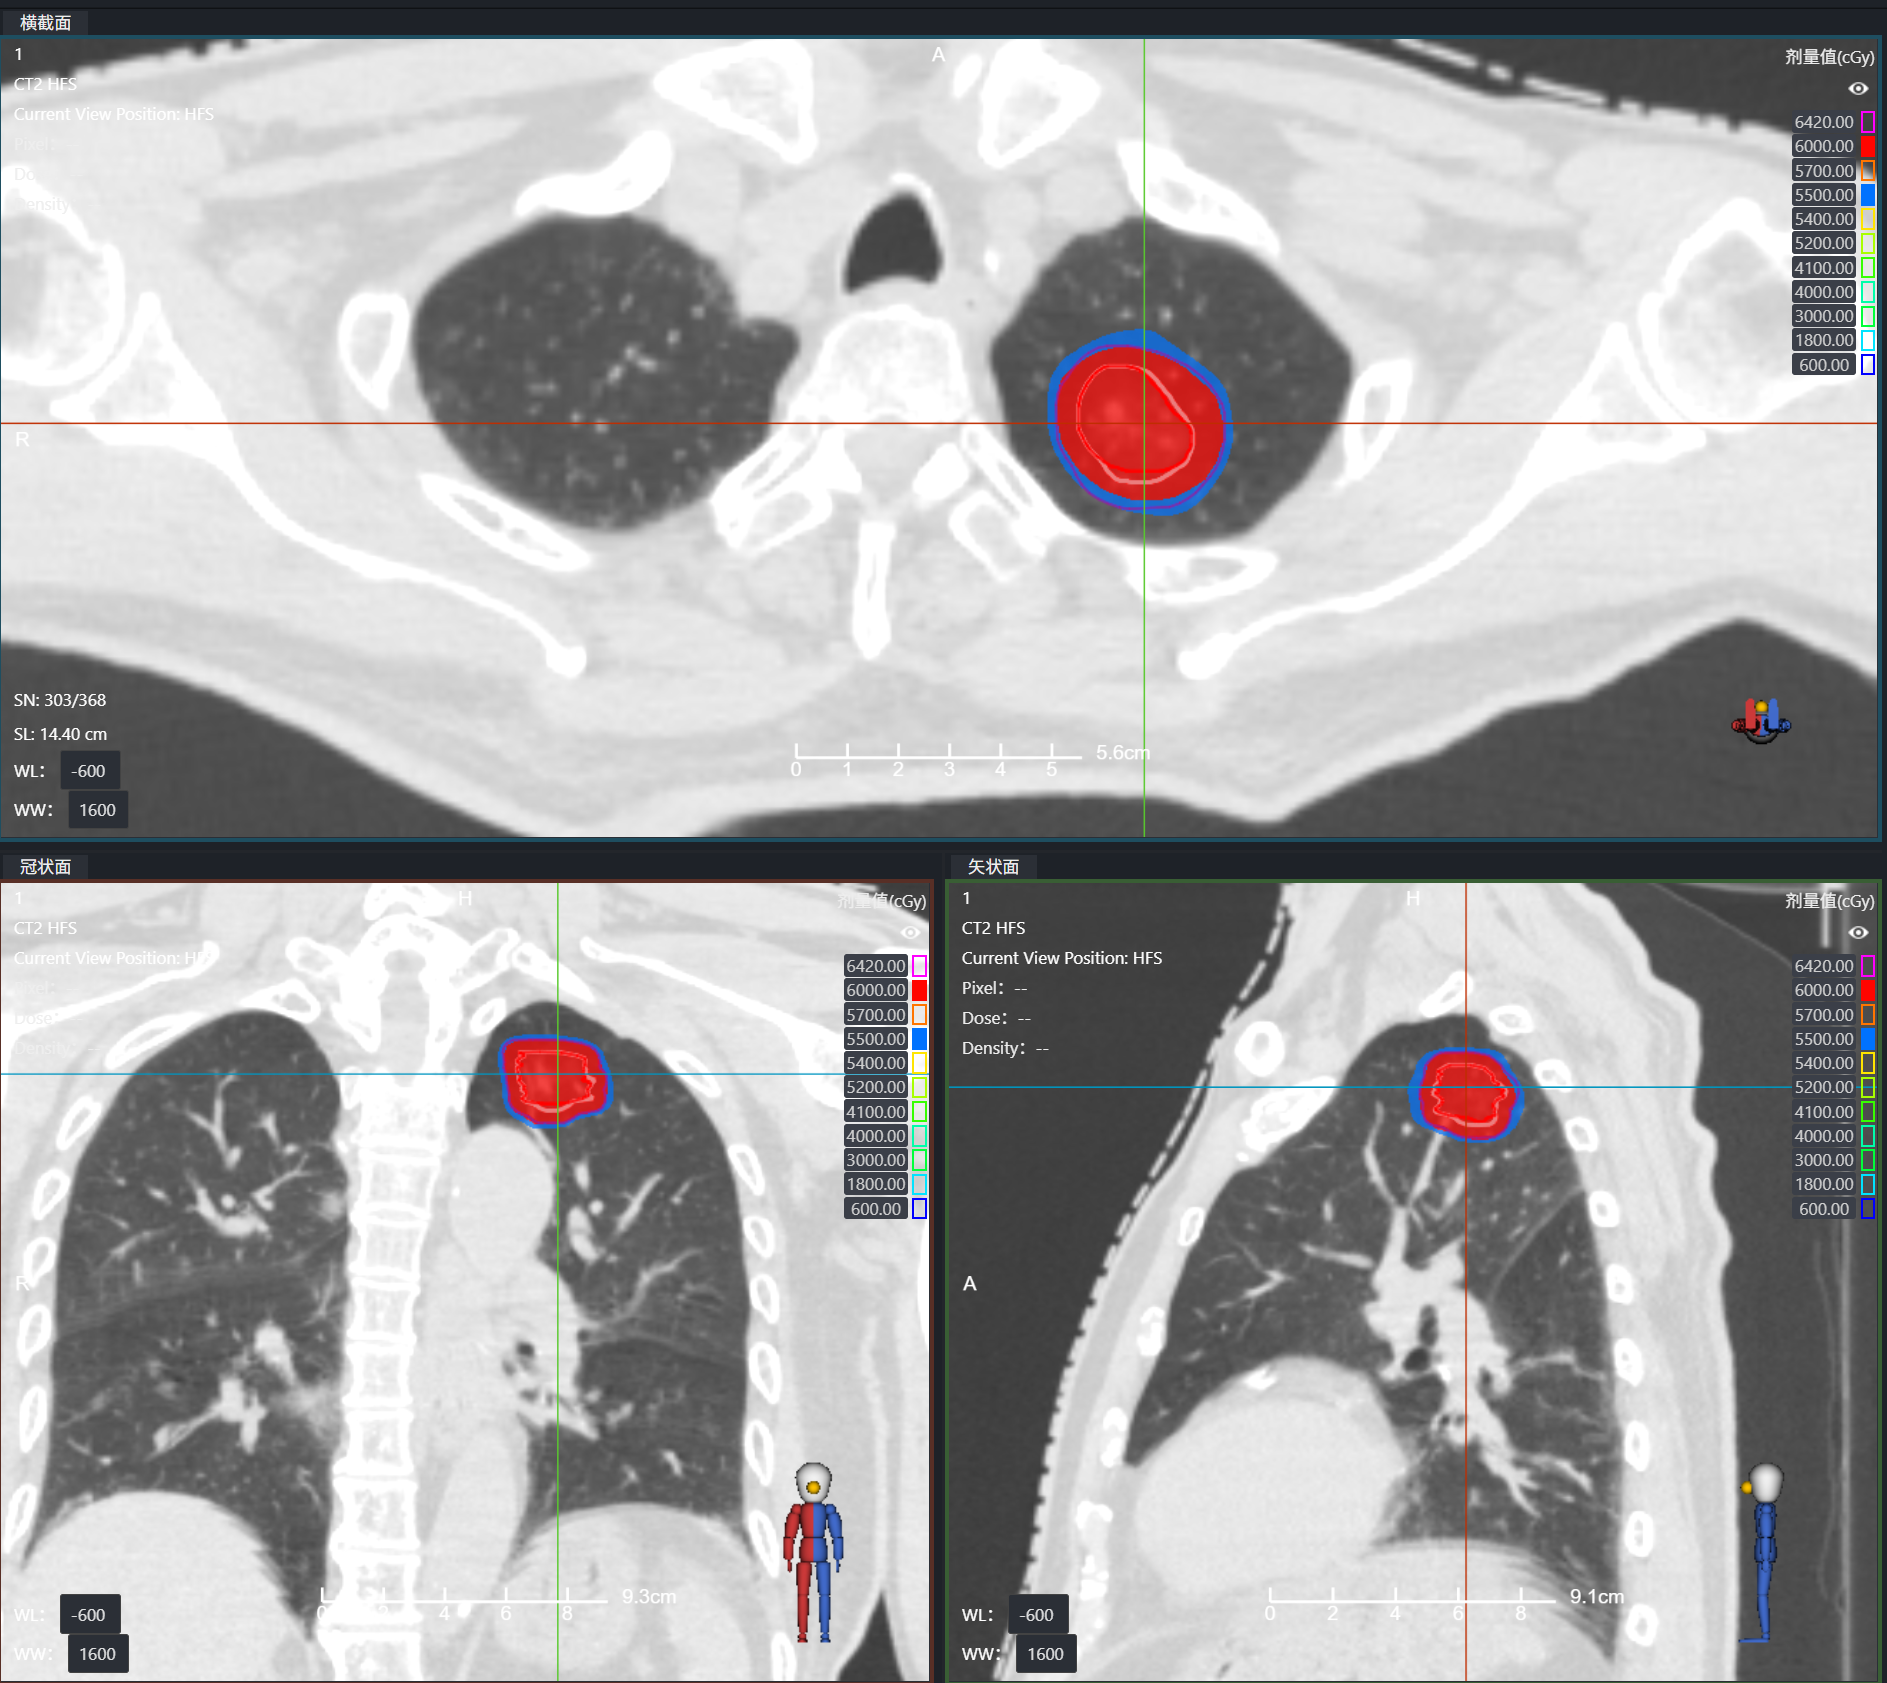

年龄与身体状况,绝非抗击癌症的阻碍!在我院,多学科协作正为高龄、无法耐受手术的肺癌患者点燃新希望。近期,两位80多岁的肺癌患者(爷爷/奶奶),通过SBRT(立体定向体部放疗)联合 4DCT(四维CT)的无创治疗,首次复查传来喜讯 —— 肺部病灶控制良好!